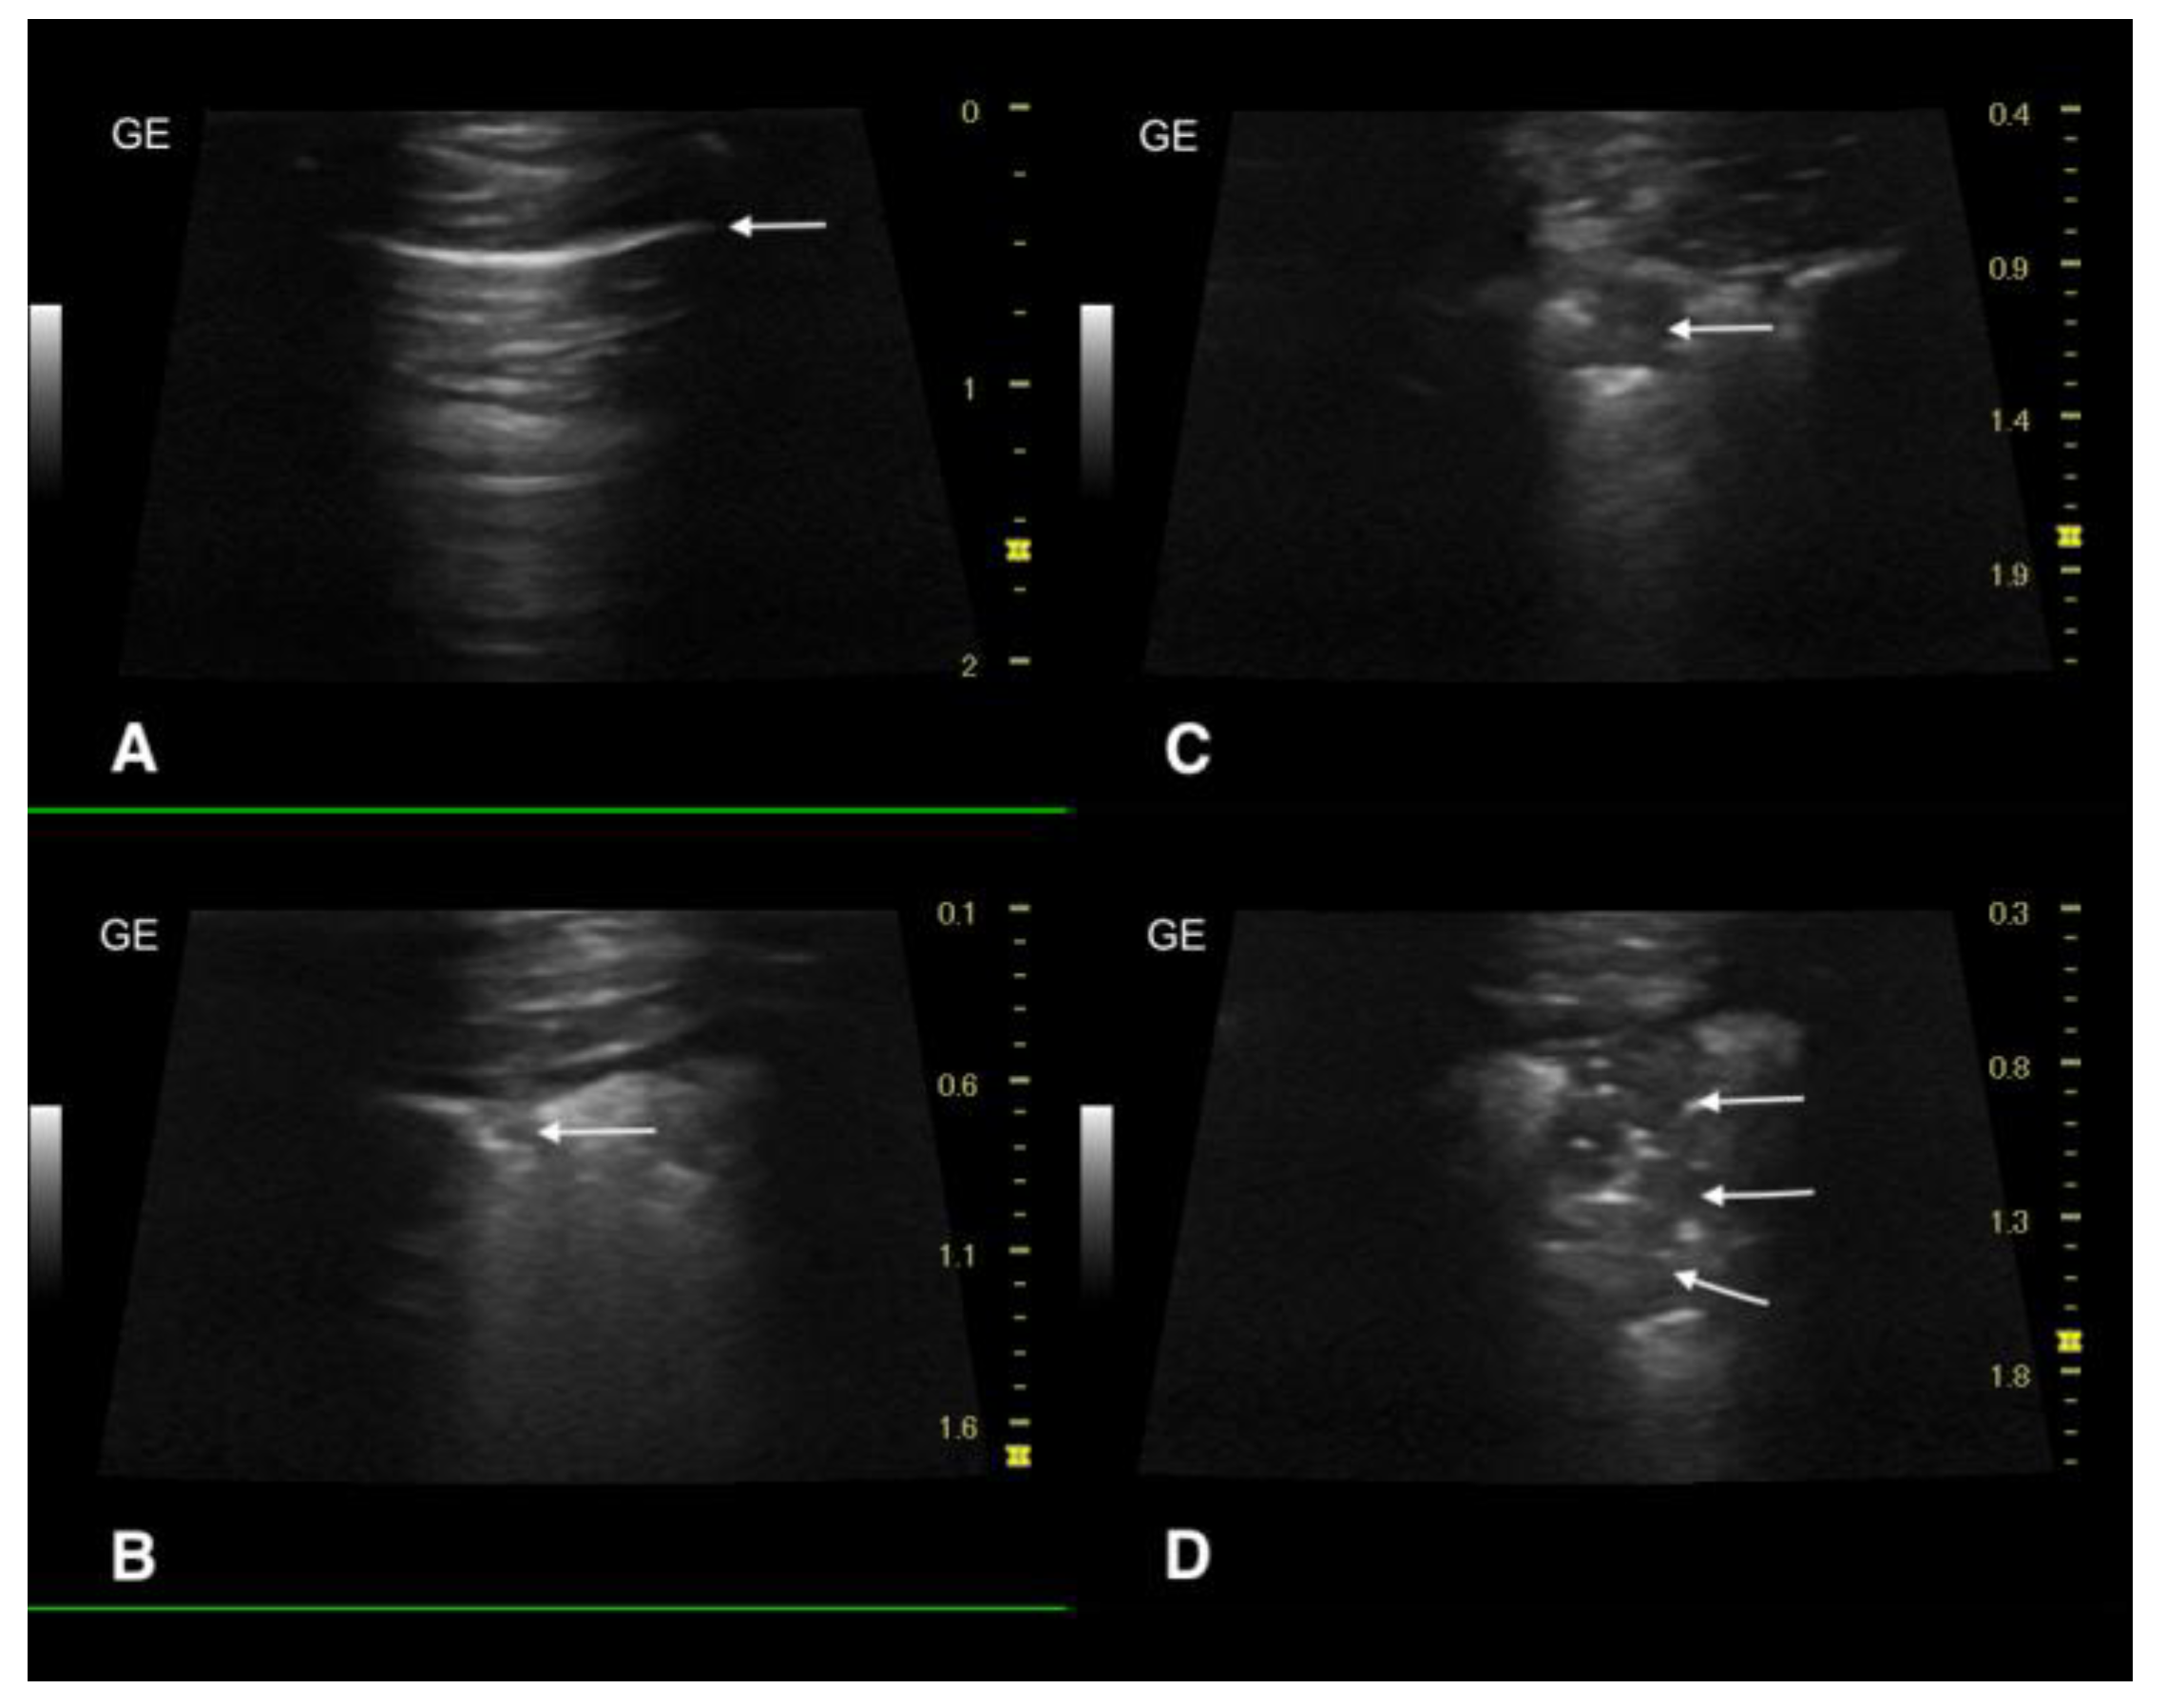

3.3. Ultrasound Examination and X-ray